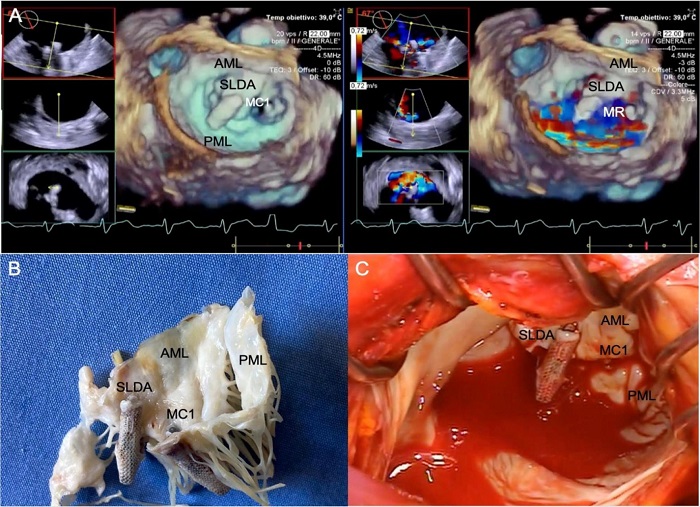

We report the case of a 79-year-old man who had undergone, 30 years before, single coronary artery bypass grafting and aortic valve replacement with a mechanical prosthesis. One month before current hospitalization, due to worsening dyspnea, he had undergone TEER for severe mitral regurgitation (MR) by MitraClipTM (MC) system (Abbott, Abbott Park, Illinois, United States of America) in a different hospital. Patient charts reported the application of two clips grasping A2 and P2 scallops, but significant MR was still evident. PA was deemed an absolute contraindication to rescue surgery and, accordingly, he was discharged on medical therapy. A few weeks later, an episode of acute heart failure despite optimal medical therapy led the patient to our emergency room. Our echocardiogram confirmed severe MR caused by posterior leaflet tear with the lateral clip grasping only the anterior leaflet (single leaflet device attachment [SLDA]) (Figure 1). A computed tomography scan confirmed the presence of PA (Video 1) and diffused calcific arteriopathy that forced us to exclude the options of an endoclamp and of circulatory arrest with antegrade cerebral perfusion through right subclavian artery cannulation. However, spots free from calcifications along the femoral arteries were judged eligible for peripheral cannulation. Despite the high surgical risk (European System for Cardiac Operative Risk Evaluation II 21.86% and Society of Thoracic Surgeons risk of morbidity or mortality 26.3%), we decided to perform a surgical correction of the TEER failure, since no effective transcatheter options were available and the patient was in good physical and cognitive status.

Cardiopulmonary bypass (CPB) was instituted through left common femoral artery and bicaval cannulation after re-sternotomy. Deep hypothermic status was the target (17.2°C nasopharyngeal temperature). CPB was interrupted and retrograde cerebral perfusion performed through the right internal jugular vein. Cold blood cardioplegia was delivered in a retrograde fashion. Mitral valve exposure through left atriotomy was partially restricted by the mechanical aortic prosthesis and the incompressible PA, thus limiting the view of the anterior annulus. Our echocardiographic suspicions were confirmed, with one clip efficiently grasping A2-P2 scallops, a SLDA (A2 lateral portion), and a torn posterior leaflet (P2 lateral portion) (Figure 1). The valve was not amenable to repair, so it was excised, and a bovine pericardial bioprosthesis was implanted. After a 40-minute DHCA, CPB was re-started. De-airing was obtained by CO2 flooding and ascending aorta venting through a needle placed in a confined area without calcifications. The postoperative period was free of major complications. Progressive improvements in both hemodynamics and physical performance were observed in the following days. Pre-discharge transthoracic echocardiography showed both aortic and mitral prostheses properly working and no paravalvular leakage, confirmed at echocardiography four months later. On the 11th postoperative day, he moved to the rehabilitation department.